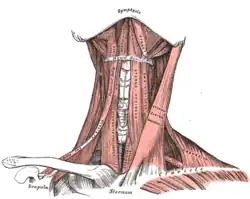

Diagram of the human shoulder joint, back view Muscles of the neck. Anterior view.

Muscles of the neck. Anterior view. Clavicle